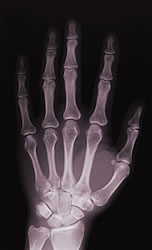

Los implantes ortopédicos se han convertido en excelentes aplicaciones de los materiales en la medicina. La investigación que se realiza en el desarrollo de nuevos biomateriales ha permitido mejorar los implantes ortopédicos con recubrimientos bioactivos procesados con láser.

Los implantes, según la composición del material, pueden ser bioinertes o bioactivos y completamente reabsorbibles. Algunas composiciones del material biocerámico y del composite son capaces de formar una fuerte unión directa con el hueso receptor. Esto se debe sobre todo a la formación en sus superficies de una capa biológicamente activa de hidroxiapatita, un compuesto de fosfato cálcico que constituye el componente mineral básico del hueso. Un grupo de universidades y empresas europeas han desarrollado un implante de rodilla de bajo coste, que presenta un ciclo de vida más largo y una mejor osteointegración. Se exploraron varios métodos para el procesamiento de la superficie con láser de alta potencia antes de obtener un revestimiento bioactivo bien adherente. Fundamentalmente, el revestimiento de fosfato cálcico resultante presenta una interfaz nivelada entre el substrato de titanio y un revestimiento de titanato de calcio, que en la superficie exterior es hidroxiapatita. Para ello se ha comprobado que lo mejor es el revestimiento de superficies con láser Nd:YAG. Las pruebas realizadas tanto dentro como fuera del cuerpo han demostrado que este tipo de revestimientos presentan una mejor citocompatiilidad y menos citotoxicidad respecto a las pruebas realizadas con el láser de CO2 . Además, se comprobó que el revestimiento con láser Nd: YAG se puede comparar estadísticamente a los materiales pulverizados con plasma. No obstante, al mismo tiempo se reduce considerablemente el coste del implante mediante la introducción de un diseño y unos instrumentos más simples. Se han desarrollado las tecnologías innovadoras tridimensionales CAD/CAM y Real Virtual Real y se han empleado para modelar, imitar y automatizar el diseño y la fabricación de las prótesis y sus recubrimientos. La reducción de costes que se consigue hace viable la producción industrial del proceso de revestimiento con láser Nd:YAG, ofreciendo al mismo tiempo una excelente oportunidad para seguir investigando, tanto en la metodología como en el desarrollo del dispositivo.